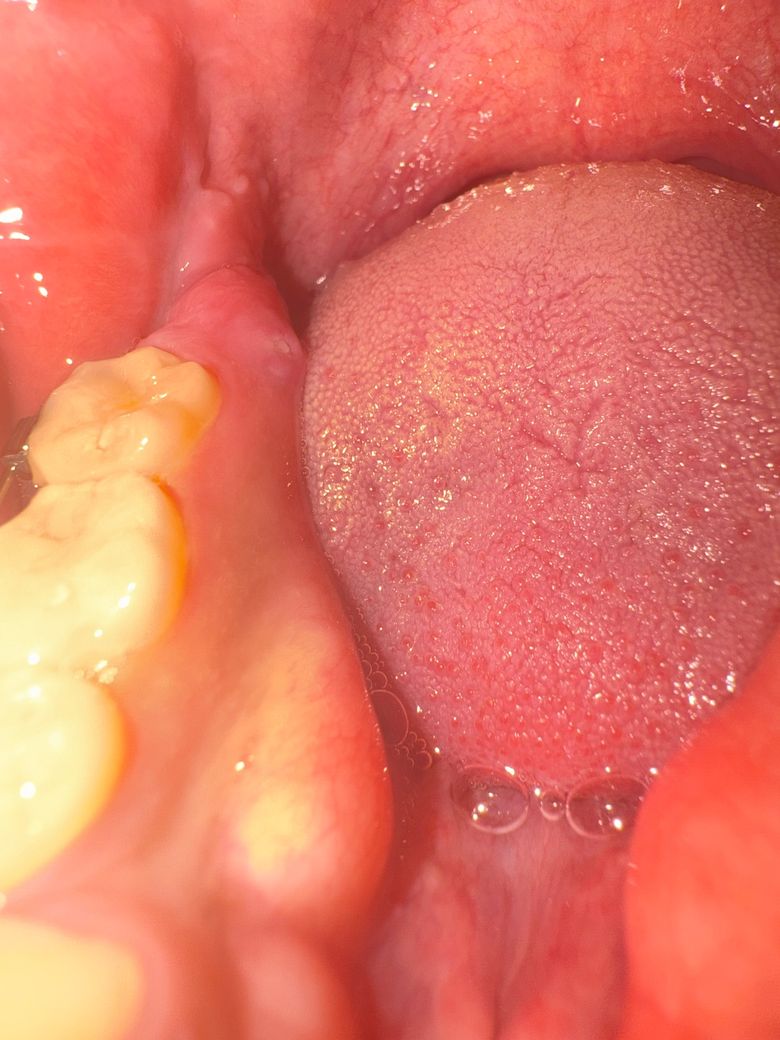

사랑니 발치 후 치조골 돌출에 관해 질문 드립니다.

사랑니 발치한지는 거의 2년된것 같은데, 사진처럼 치조골 돌출이 생긴것 같아요. 조금 거슬리고 딱딱한 음식을 먹으면 자극이 된것처럼 살짝 통증이 있습니다. 간단한 치료면 된다고 들었는데, 제가 미국에 나와있어서 당장 치과에 가기는 부담이 되어서 한달뒤에 한국에 들어갈때까지 놔둬도 될까요?

• 1번 째 사진

앞쪽 돌출 구조물은 치조골융기(torus)로 정상구조이고, 아마도 말씀하시는 건 어금니 뒤쪽 (사랑니가 있던 쪽) 잇몸 튀어나온 것 때문에 그러시는 것 같은데 단순 골 증식으로 인한 융기일 수도 있고, 다른 병소일 수도 있습니다. 표면에 궤양은 자극이 되어 생긴 것 같습니다. 그거보다 내부 골 증식이 왜 발생했는지 확인해보면 좋을 것 같습니다. 골 증식이 잘 생기는 부위가 아니긴 합니다.

표면 궤양은 오라메디 등 약국에서 입 안에 적용하는 연고 바르세요. 귀국해서 검사해보세요.